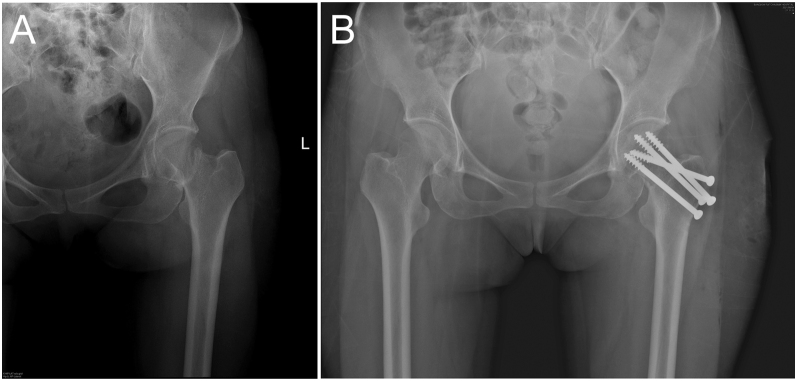

摘要:醋酸甲羟孕酮(DMPA)是一种高效的注射避孕药,但在一些研究中,由于它抑制下丘脑-垂体-卵巢轴,因此与骨密度(BMD)降低和骨折风险增加有关。在此,我们提出诊断具有挑战性的情况下,绝经前妇女不寻常的髋部骨折和长期使用肌内注射DMPA。全外显子组测序揭示了一种罕见的ALPL基因杂合变异,该变异可能导致成人发病的低磷酸盐症(HPP)。然而,它被归类为一个未知意义的变体。我们的病例强调了长期使用DMPA的骨折风险,DMPA在低收入和中等收入国家广泛用作仅使用孕激素的避孕方法。临床医生应告知妇女长期使用DMPA避孕对骨骼健康的潜在不利影响,并建议她们养成健康的生活习惯,摄入足够的钙和维生素D。学习要点:有证据表明肌内注射醋酸甲羟孕酮(DMPA)通过抑制下丘脑-垂体-卵巢轴对骨密度产生负面影响。然而,由于缺乏骨折发生率的数据,DMPA导致骨脆性骨折的风险仍然不确定。在这里,我们提出了一个绝经前妇女不寻常的髋部骨折和长期使用肌内DMPA避孕的历史。我们的病例也强调了患者的临床表现是解释基因测序结果的关键。

Summary: Depot medroxyprogesterone acetate (DMPA) is a highly effective injectable contraceptive, but is associated with reduced bone mineral density (BMD) and increased fracture risk in some studies because it inhibits the hypothalamic-pituitary-ovarian axis. Herein, we present the diagnostic challenging case of a premenopausal woman with an unusual hip fracture and prolonged use of intramuscular DMPA injection. Whole-exome sequencing revealed a rare heterozygous variant of the ALPL gene, which could cause adult-onset hypophosphatasia (HPP). However, it was classified as a variant of unknown significance. Our case highlights the fracture risk from long-term use of DMPA, which is widely used as progestogen-only contraceptive method in low- and middle-income countries. Clinicians should inform women on the potential adverse effect of prolonged use of DMPA for contraception on bone health and advise them to adopt healthy lifestyle habits, with adequate calcium and vitamin D intake.

Learning points: Evidence shows that intramuscular depot medroxyprogesterone acetate (DMPA) negatively affects BMD by inhibiting the hypothalamic-pituitary-ovarian axis. However, the risk of bone fragility fracture from DMPA remains uncertain because of paucity of data on fracture incidence. Herein, we present a case of a premenopausal woman with an unusual hip fracture and a history of prolonged use of intramuscular DMPA contraception. Our case also highlights that the patient's clinical presentation is essential for interpreting genetic sequencing results.